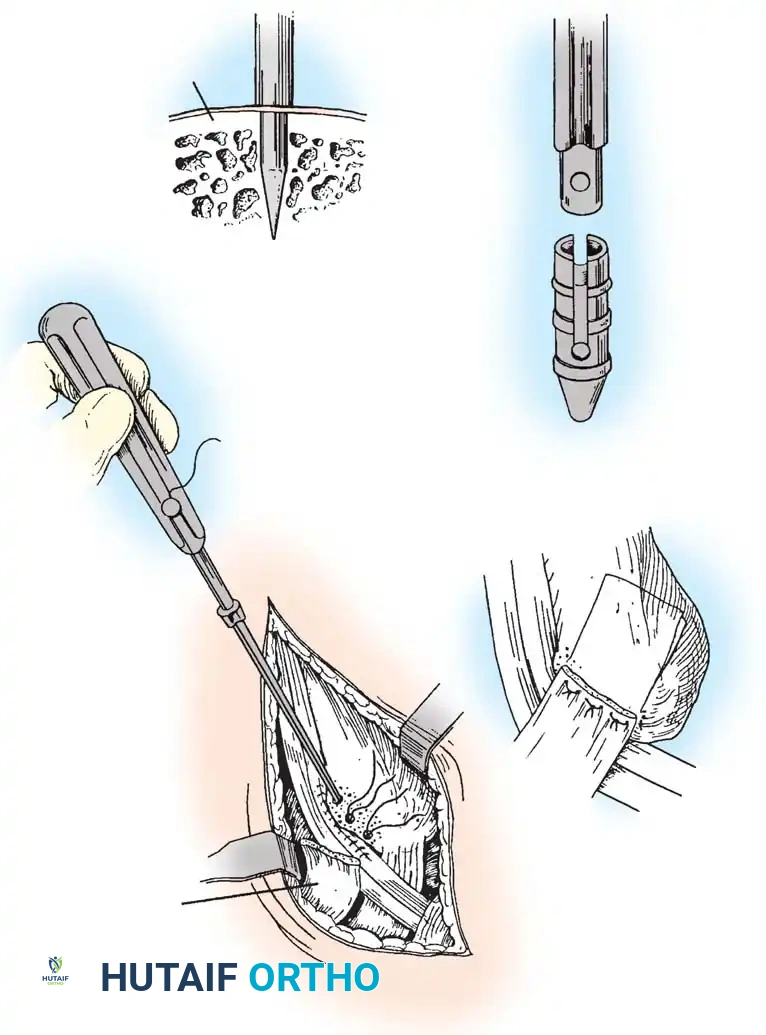

Operative Technique: Synovectomy and Repair of Peroneal Tendons (Technique 85-9)

1. Patient Positioning and Anesthesia

The procedure is performed under general or regional anesthesia. The patient is placed in the lateral decubitus position, or supine with a large bolster beneath the ipsilateral hip to internally rotate the leg, allowing excellent access to the lateral ankle. The foot is held in equinovalgus to relax the peroneal tendons. A thigh tourniquet is applied and inflated after exsanguination.

2. Surgical Approach

Begin the incision 10 to 12 cm proximal to the tip of the lateral malleolus, positioned approximately 1 cm posterior to the subcutaneous border of the fibula. Continue the incision distally and slightly obliquely to accommodate the bulbous posterior aspect of the lateral malleolus. Curve the incision gently 1 cm distal to the tip of the lateral malleolus, extending toward the base of the fifth metatarsal for another 3 to 4 cm.

Surgical Pitfall: The sural nerve and the small saphenous vein course just posterior to the peroneal tendons and are strictly subcutaneous at this level. Meticulous dissection is required to avoid iatrogenic neuroma formation, which can be more debilitating than the primary tendon pathology.

3. Retinaculum Release and Exploration

Open the sheath of the peroneal tendons proximally and trace the tendons distally to the superior peroneal retinaculum (SPR).

- If the tendons appear normal both proximal and distal to the SPR, incise only half of the retinaculum (about 1 cm or less) to preserve its stabilizing function.

- If the SPR is thickened or the sheath is fibrotic—suggesting impaired tendon excursion—incise the entire retinaculum and inspect the inferior peroneal retinaculum (IPR). In isolated tenosynovitis, it is unusual to require the release of both retinacula.

Carefully evaluate the septum that extends from the fibula to the SPR, separating the peroneus longus and brevis. An accessory peroneal tendon (peroneus quartus) may be present in a separate compartment, contributing to overcrowding and stenosis. Release this septum and inspect the peroneus brevis, looking for any accessory slips.

4. Tenosynovectomy and Tendon Debridement

Perform a complete tenosynovectomy, sharply debriding hypertrophic portions of the tendon sheath with a small rongeur or dissecting scissors. The findings at surgery represent a continuum: from clear fluid and relatively normal-appearing tendons, to small linear tears, to thickened, fibrotic sheaths encasing grayish, degenerative tendons.

Inspect the tendons meticulously for attritional, longitudinal fissuring. This pathology is most commonly located on the deep (anterior) surface of the peroneus brevis tendon, where it is compressed against the fibula by the overlying peroneus longus.

5. Tendon Repair Based on Tear Grade

For Grade I Tears (≤ 50% involvement):

If the tear involves less than 50% of the tendon's cross-sectional area, excise the smaller, degenerative section of the tendon completely. The remaining viable portion is then tubularized to restore a smooth gliding surface. This is achieved using a running 3-0 absorbable, braided suture, burying the knots to minimize friction.

For Grade II Tears (> 50% involvement):

If more than 50% of the peroneus brevis tendon is disrupted and fissured, the remaining section is generally too attenuated to be tubularized effectively. In this scenario, resect the entire diseased segment of the peroneus brevis.

Perform a side-to-side tenodesis of the proximal and distal stumps of the peroneus brevis to the intact peroneus longus tendon.

* The proximal tenodesis should be performed well above the level of the SPR, approximately 3 to 4 cm proximal to the ankle joint, generally at the musculotendinous junction of the peroneus brevis.

* Complete the repair using 2-0 nonabsorbable, braided sutures (e.g., Ethibond or FiberWire), ensuring appropriate tension is maintained to preserve eversion strength.

6. Closure

Distally, leave the tendon sheaths for both the brevis and longus open to prevent postoperative stenosis. Suture the brevis and longus tendons together distally with 2-0 nonabsorbable sutures if a tenodesis was performed.

Repair the superior peroneal retinaculum over the tendons using 2-0 absorbable sutures, ensuring the tendons do not subluxate during passive dorsiflexion and eversion. Leave the remainder of the tendon sheath open. Close the subcutaneous tissues and skin in a standard layered fashion.